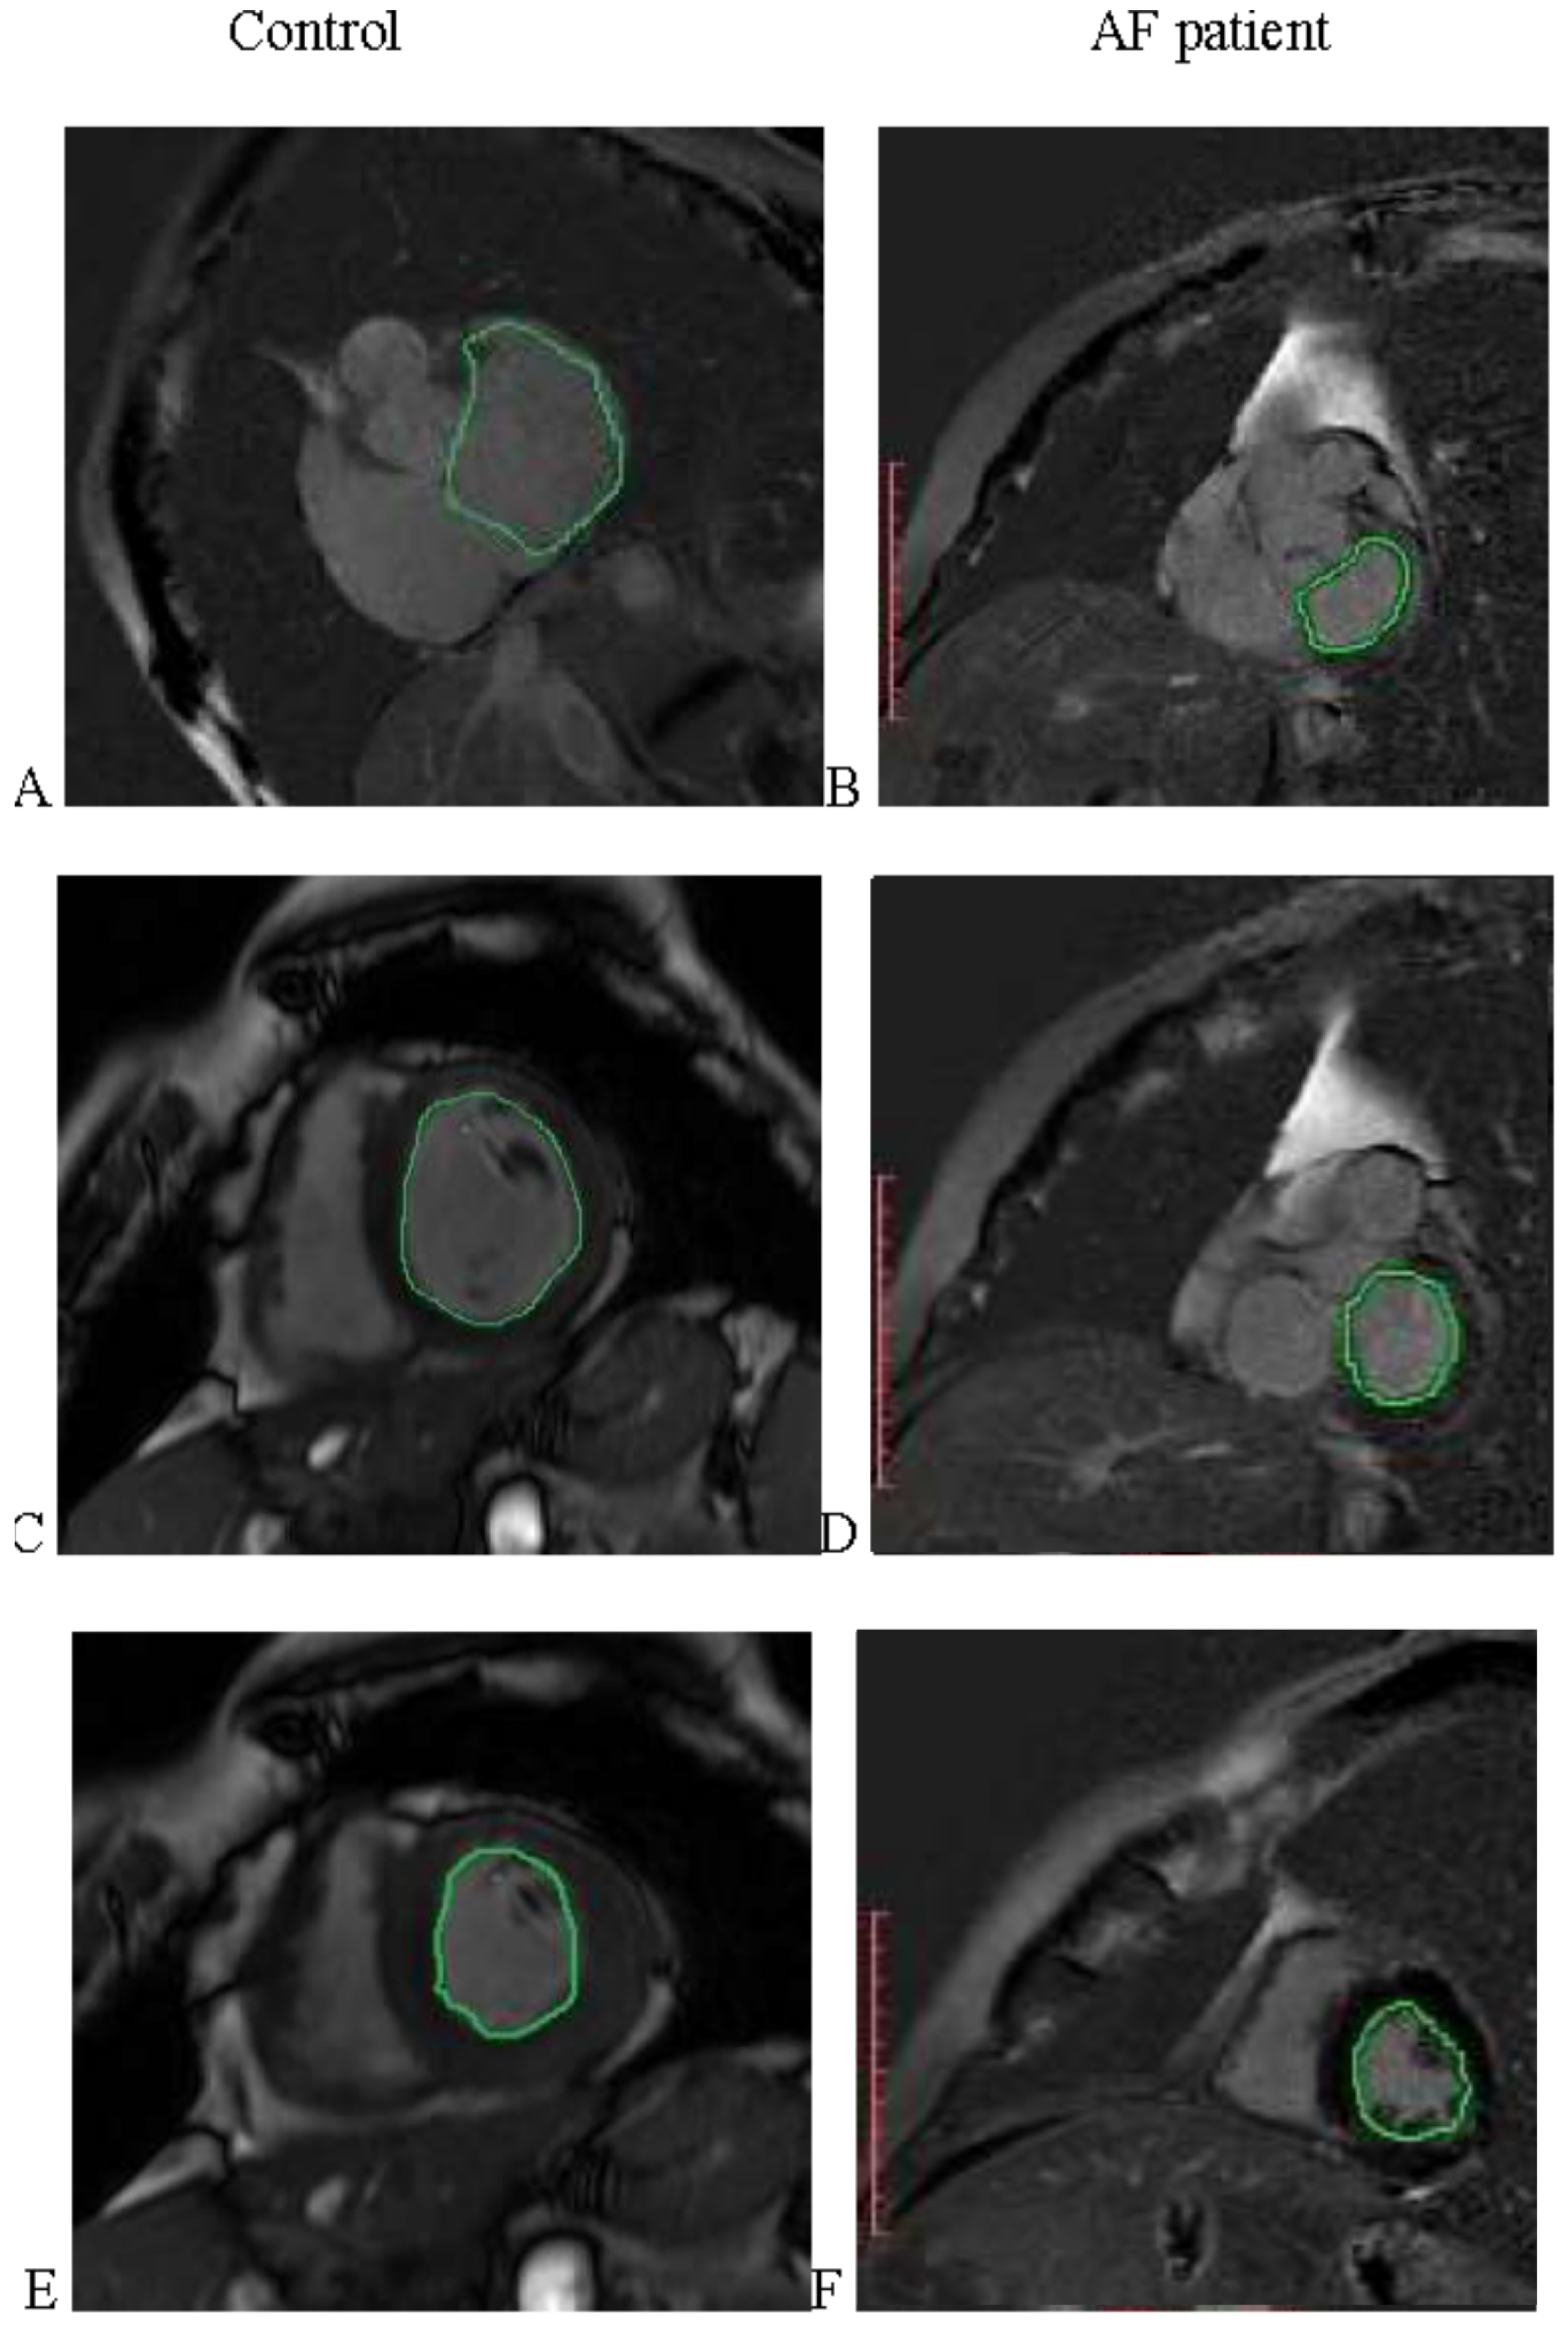

2.2. MRI Acquisition

| EDV (mL) | |||

| All | 130.5 (113.9–160.6) | 90.1 (77.65–102.5) | <0.0001 |

| Controls | 128.8 (106.8–159.9) | 94.75 (80.3–103.2) | <0.0001 |

| AF patients | 135.6 (114.4–162.1) | 88.6(77.4–100.9) | <0.0001 |

| ESV (mL) | |||

| All | 52.4 (36.9–69.7) | 39.3 (30.95–44.55) | <0.0001 |

| Controls | 44.2 (35.1–54.7) | 36.25 (28.4–41.65) | 0.0015 |

| AF patients | 60.1 (44.31–76.7) | 36.3 (31.6–47.4) | <0.0001 |

| EF (%) | |||

| All | 61.3 (53.2–68.4) | 59.1 (54.15–62.8) | 0.10 |

| Controls | 65.6 (61.9–71.6) | 61.05 (57.63–66.7) | 0.003 |

| AF patients | 55.4 (47.5–64.85) | 56.7 (50.9–62.0) | 0.93 |